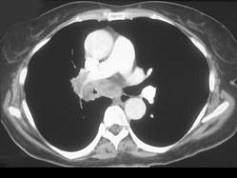

问题 男,56岁,咳嗽,咯血1月余,有吸烟史30余年,结合CT检查选出最可能的诊断 ( )

选项 A、肺错构瘤 B、中央型肺癌 C、肺炎 D、结节病 E、肺结核

答案 B